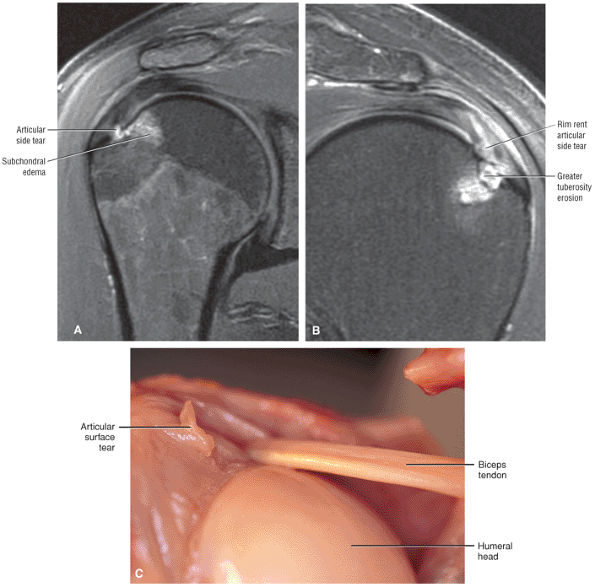

![]() |

FIGURE 8.32 Rotator Cuff.

FIGURE 8.33 Acromioclavicular Joint.

FIGURE 8.34 Biceps Tendon.

FIGURE 8.35 Labrum.

FIGURE 8.36 IGL.

FIGURE 8.37 Glenohumeral Joint.

FIGURE 8.38 Osseous.

FIGURE 8.39 Deltoid Muscle.